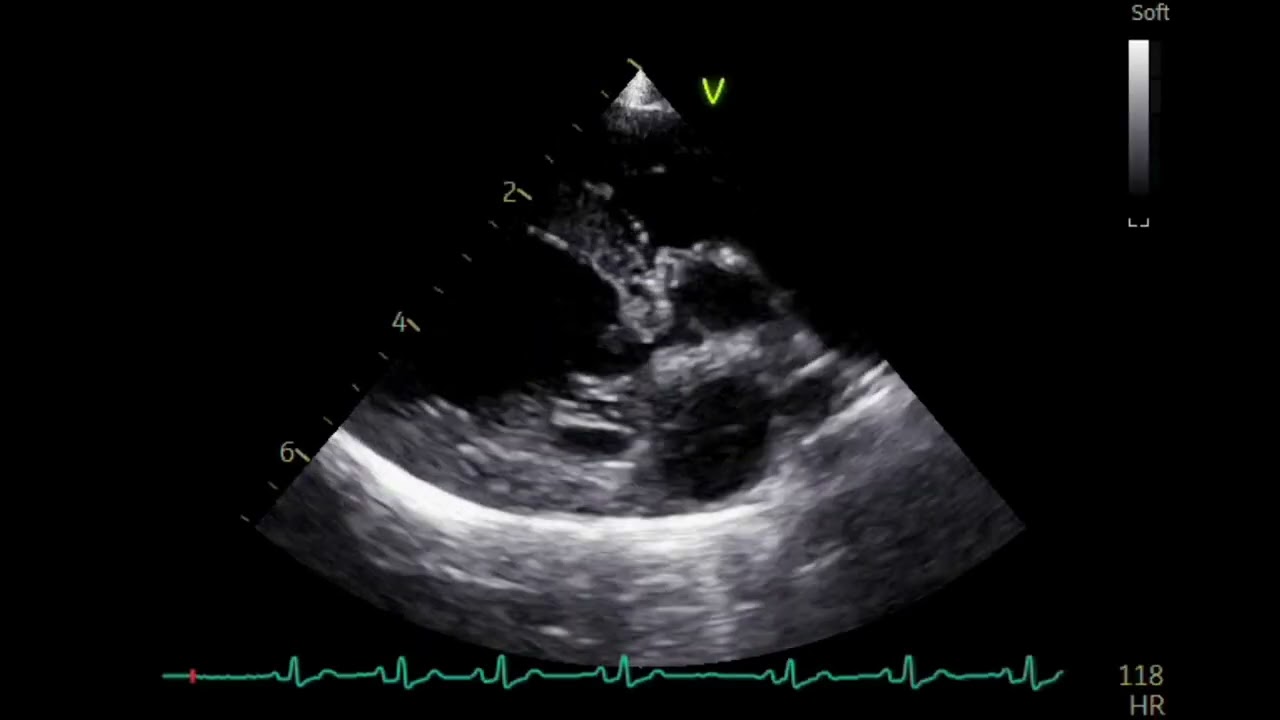

Mitral Valve , Pocket size VS Stationary high end system echo images、dog(2kg)犬の僧帽弁のポケットエコー